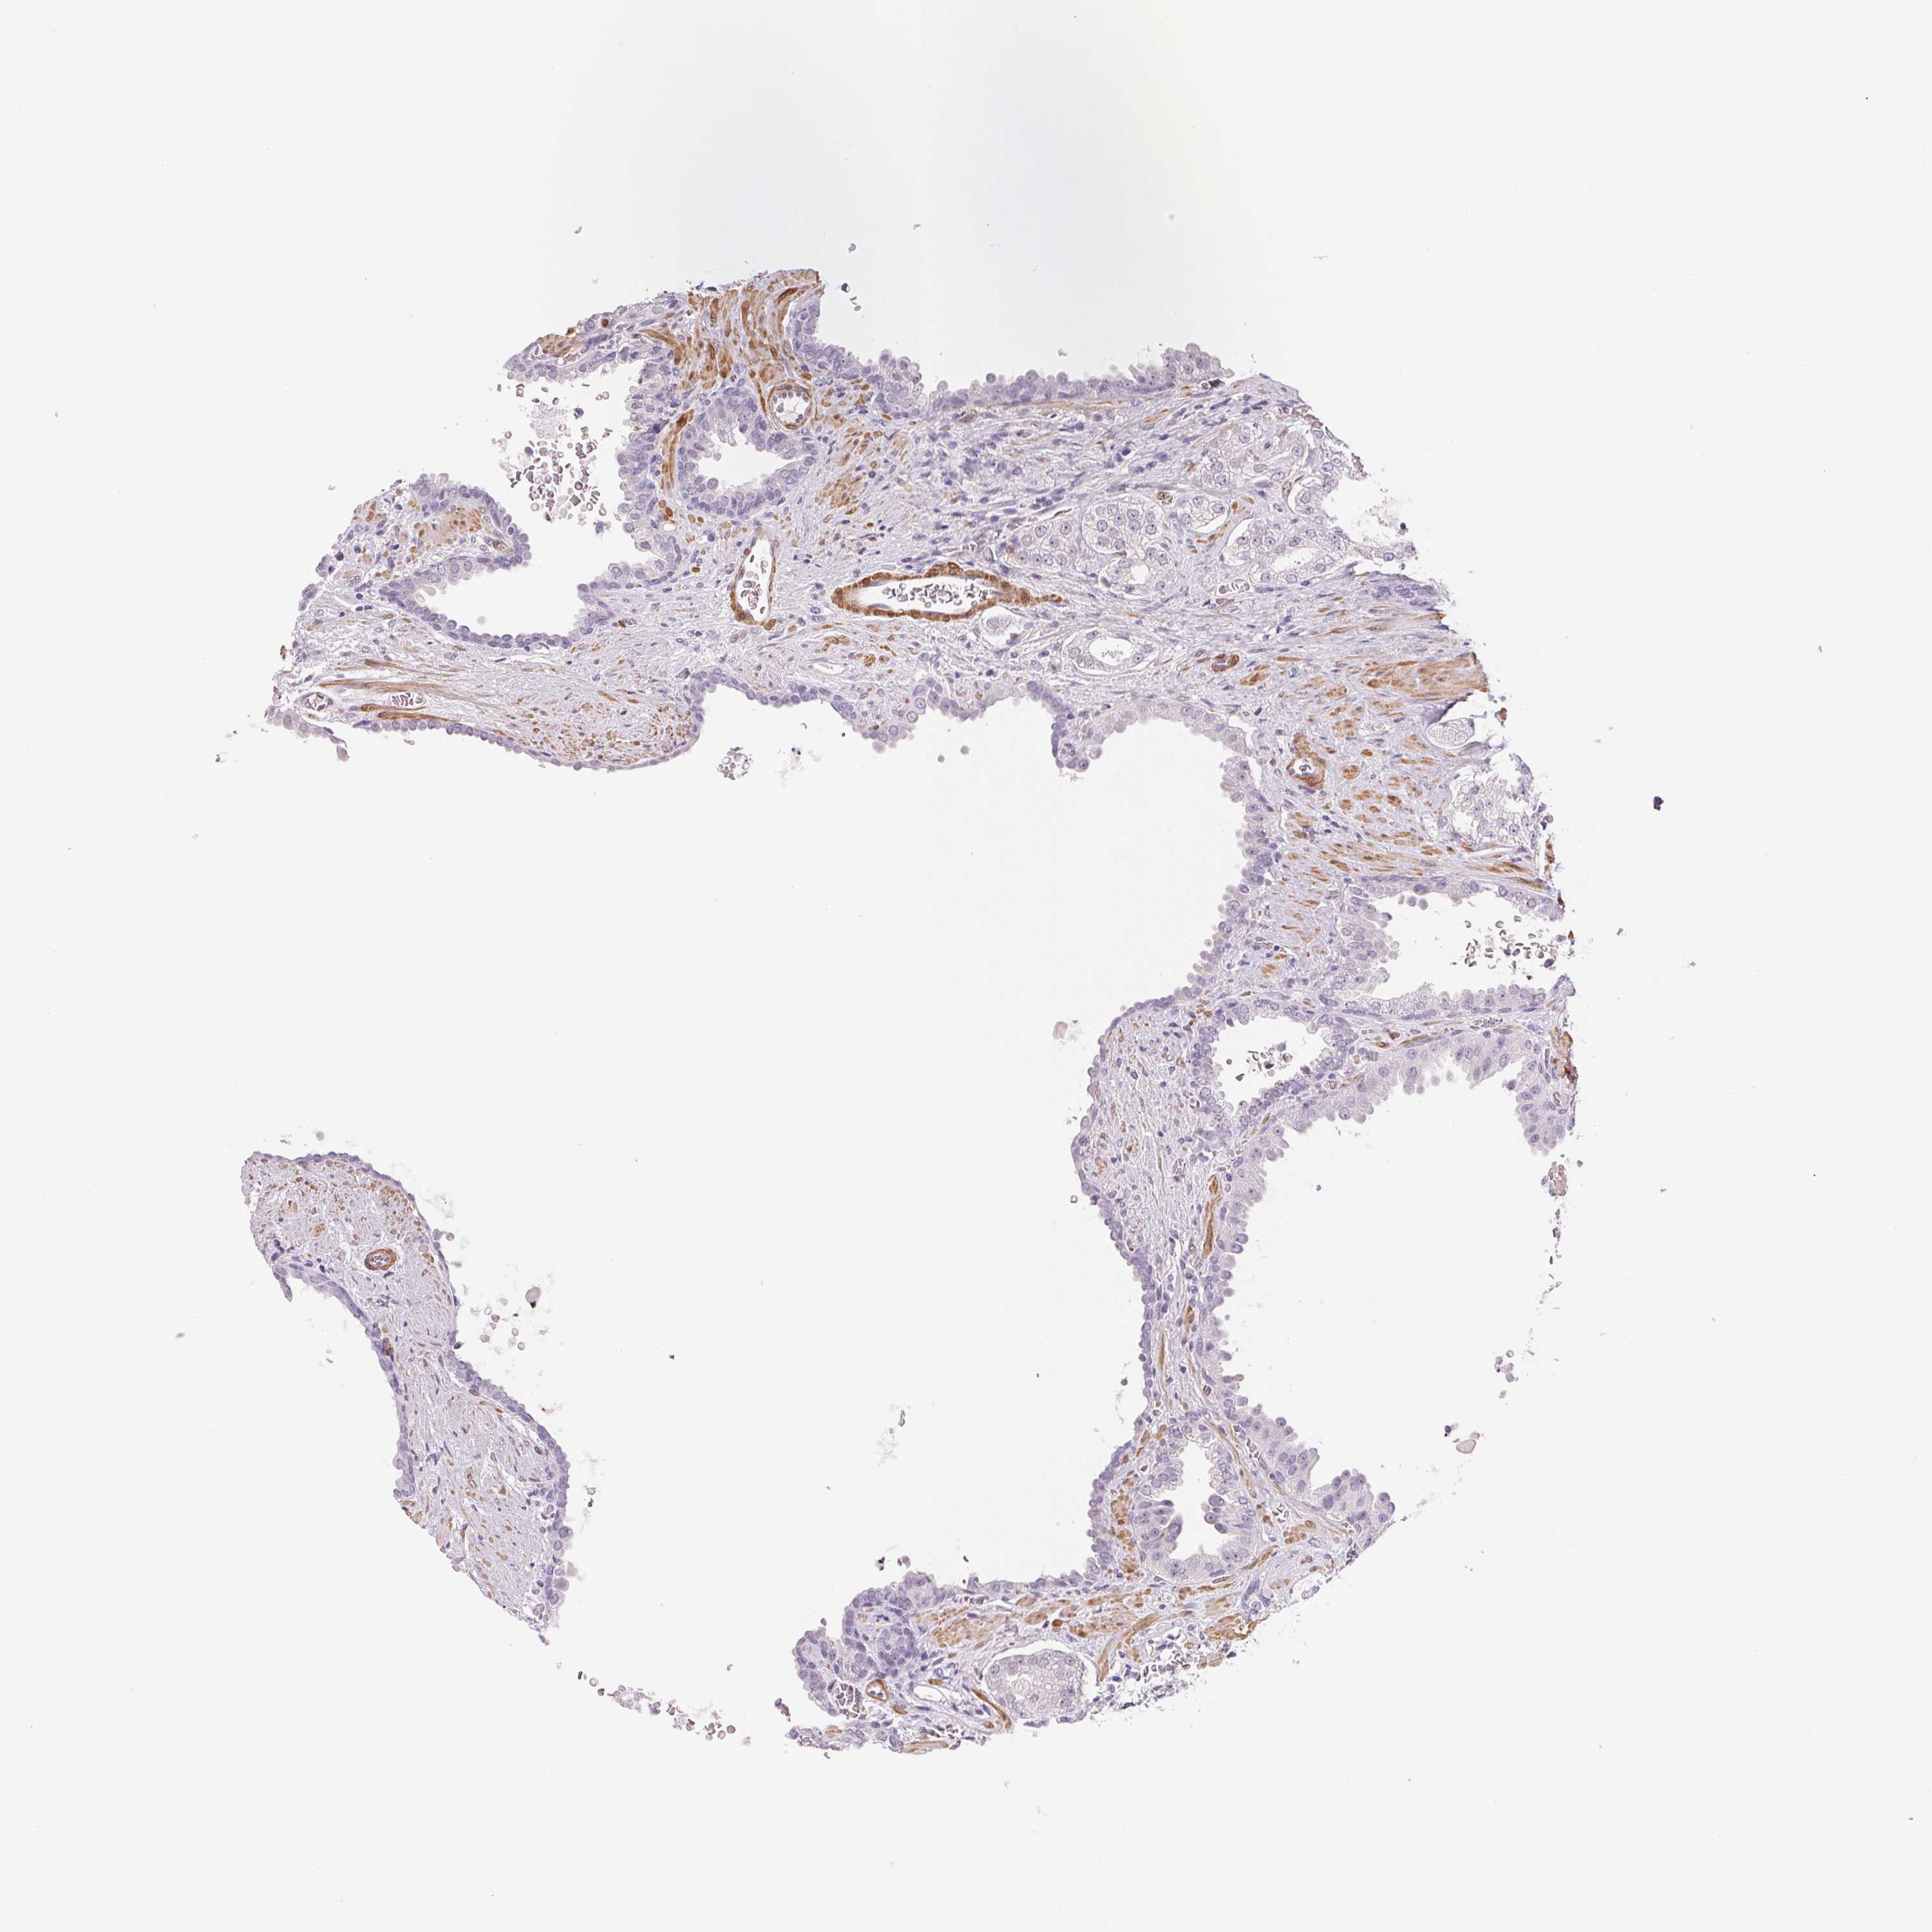

PROSTATE CANCER - Protein expressioni

A mouse-over function shows sample information and annotation data. Click on an image to view it in a full screen mode. Samples can be filtered based on level of antibody staining by selecting one or several of the following categories: high, medium, low and not detected. The assay and annotation is described here.

Note that samples used for immunohistochemistry by the Human Protein Atlas do not correspond to samples in the TCGA dataset.

Antibody stainingi

Antibody staining in the annotated cell types in the current human tissue is reported as not detected, low, medium, or high, based on conventional immunohistochemistry profiling in selected tissues. This score is based on the combination of the staining intensity and fraction of stained cells.

Each image is clickable and will lead to virtual microscopy that enables deeper exploration of all samples and also displays staining intensity scores, fraction scores and subcellular localization as well as patient and tissue information for each sample.

Antibody HPA051778

Antibody HPA058590

Antibody CAB001721

Adenocarcinoma, High grade

Adenocarcinoma, NOS

Adenocarcinoma, Low grade